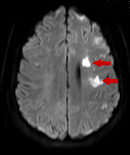

Findings of an MRI scan of the head were significant for multifocal bilateral subacute infarcts, predominantly scattered throughout the left cerebral hemisphere with superimposed multifocal remote infarcts, and vessel occlusion (Figures 1-3).

Figure 1. Diffusion-weighted MRI scan showing infarcted cerebral tissue, indicated by areas of high signal intensity.